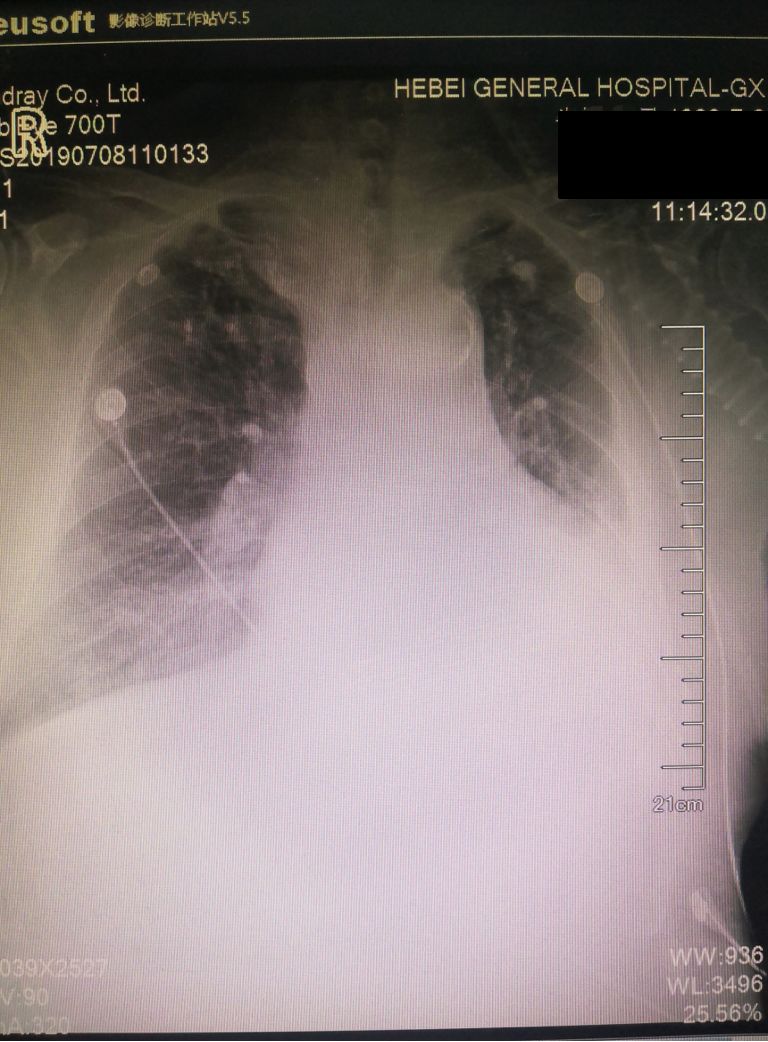

治疗后